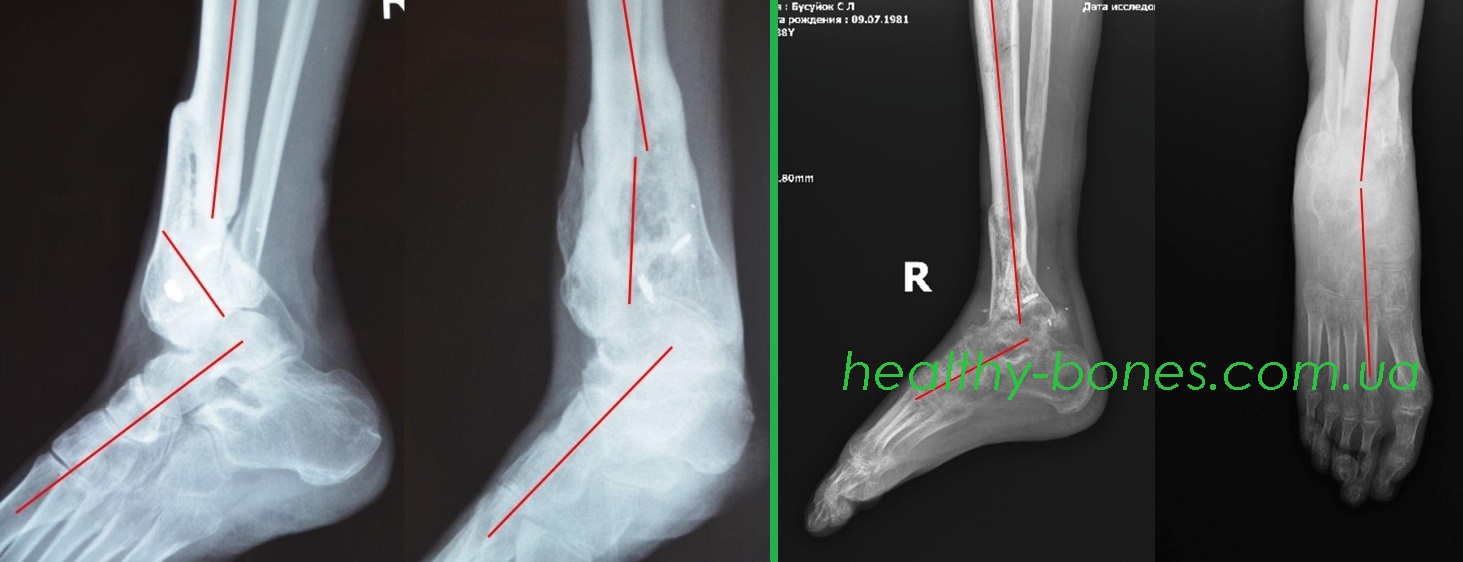

В результаті бойових дій в зоні проведення АТО отримав осколкове поранення гомілки з багатоосколковим переломом дистальної третини правої великогомілкової кістки і надлодижечний перелом малогомілкової кістки. Лікувався у військовому госпіталі. Переломи зрослися з укороченням і складними кутовими і ротаційної деформацією.

Нами були проведені етапні операції, спрямовані на усунення всіх видів деформації і укорочення кінцівки. Через 2 роки після початку лікування Сергій зміг повноцінно користуватися своєю правою ногою.